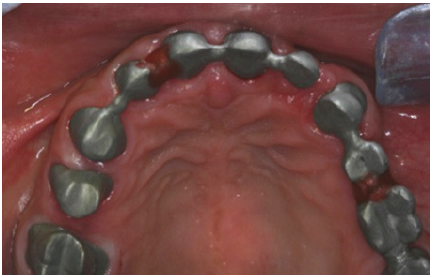

The final preparations were observed in two study casts to improve the parallelism and ensure accurate path of the insertion for the final prostheses. Final preparations and relining of the provisional restorations followed. Final impressions were performed using polyvinyl-siloxane (Aquasil, Dentsply, Germany) with the two-step double mixing technique (stock tray, double cord technique) in the maxilla. Mandibular impression was performed with an open tray technique combining implant and teeth abutments with polyether material (Impregum, 3M, USA). In next appointment the accuracy of final casts was examined and jaw relation recordings were performed. The position of maxillary cast was transferred with a Whip-Mix face bow and centric relation (CR) was registered with a custom made acrylic Lucia jig (anterior deprogrammer) and an implant retained base plate in the mandible to ensure accurate registration. Dental and implant abutments metal try-in were completed in two steps (Figure 16). After thorough verification of accuracy of fit and jaw registrations, ceramic veneering was checked for proper occlusion (Figure 17,18). Finally all restorations were cemented with adhesive resin cement (Panavia F2.0, Kuraray, Japan), except for the implant restorations which were cemented with a provisional cement (Temp-bond, Kerr, Germany).

Figure 16: Dental abutments metal try in the maxilla.

Figure 17: Final restorations occlusal view of the maxilla.